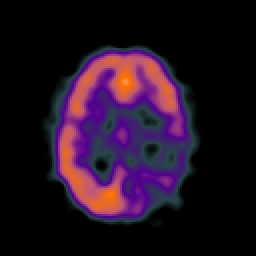

SPECT TC Study #4 -- Slice #35

[Home][Help][Clinical][Tour 1][Tour 2][Tour 3] Slice 35